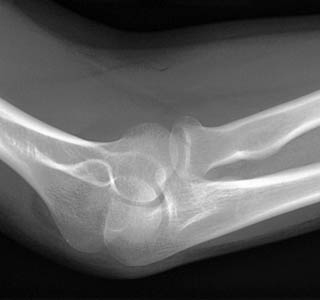

11) What abnormalities of the elbow can be observed in the image below?

12) Based on your findings, what fracture is shown in the above image?